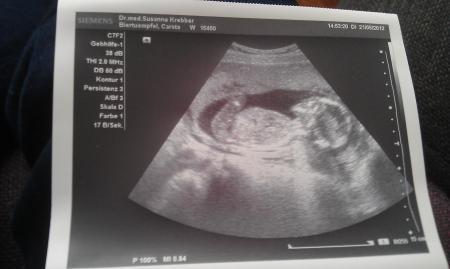

Komme gerade vom Arzt, eigentlich wollte Sie sich so früh noch nicht festlegen und man sah das Kind von der Seite aber just in dem Moment dreht sich das Kind und man sah das Geschlechtsteil...Es wird zu 100% ein Junge...160Gramm und 11cm...alles in Ordnung